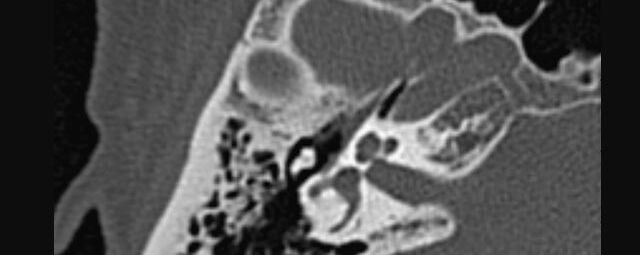

Kopf

• Schlaganfalldiagnostik

• Traumadiagnostik (Akutdiagnostik nach Verletzungen, Unfällen)

• Nasennebenhöhlen (Entzündungen, Tumore)